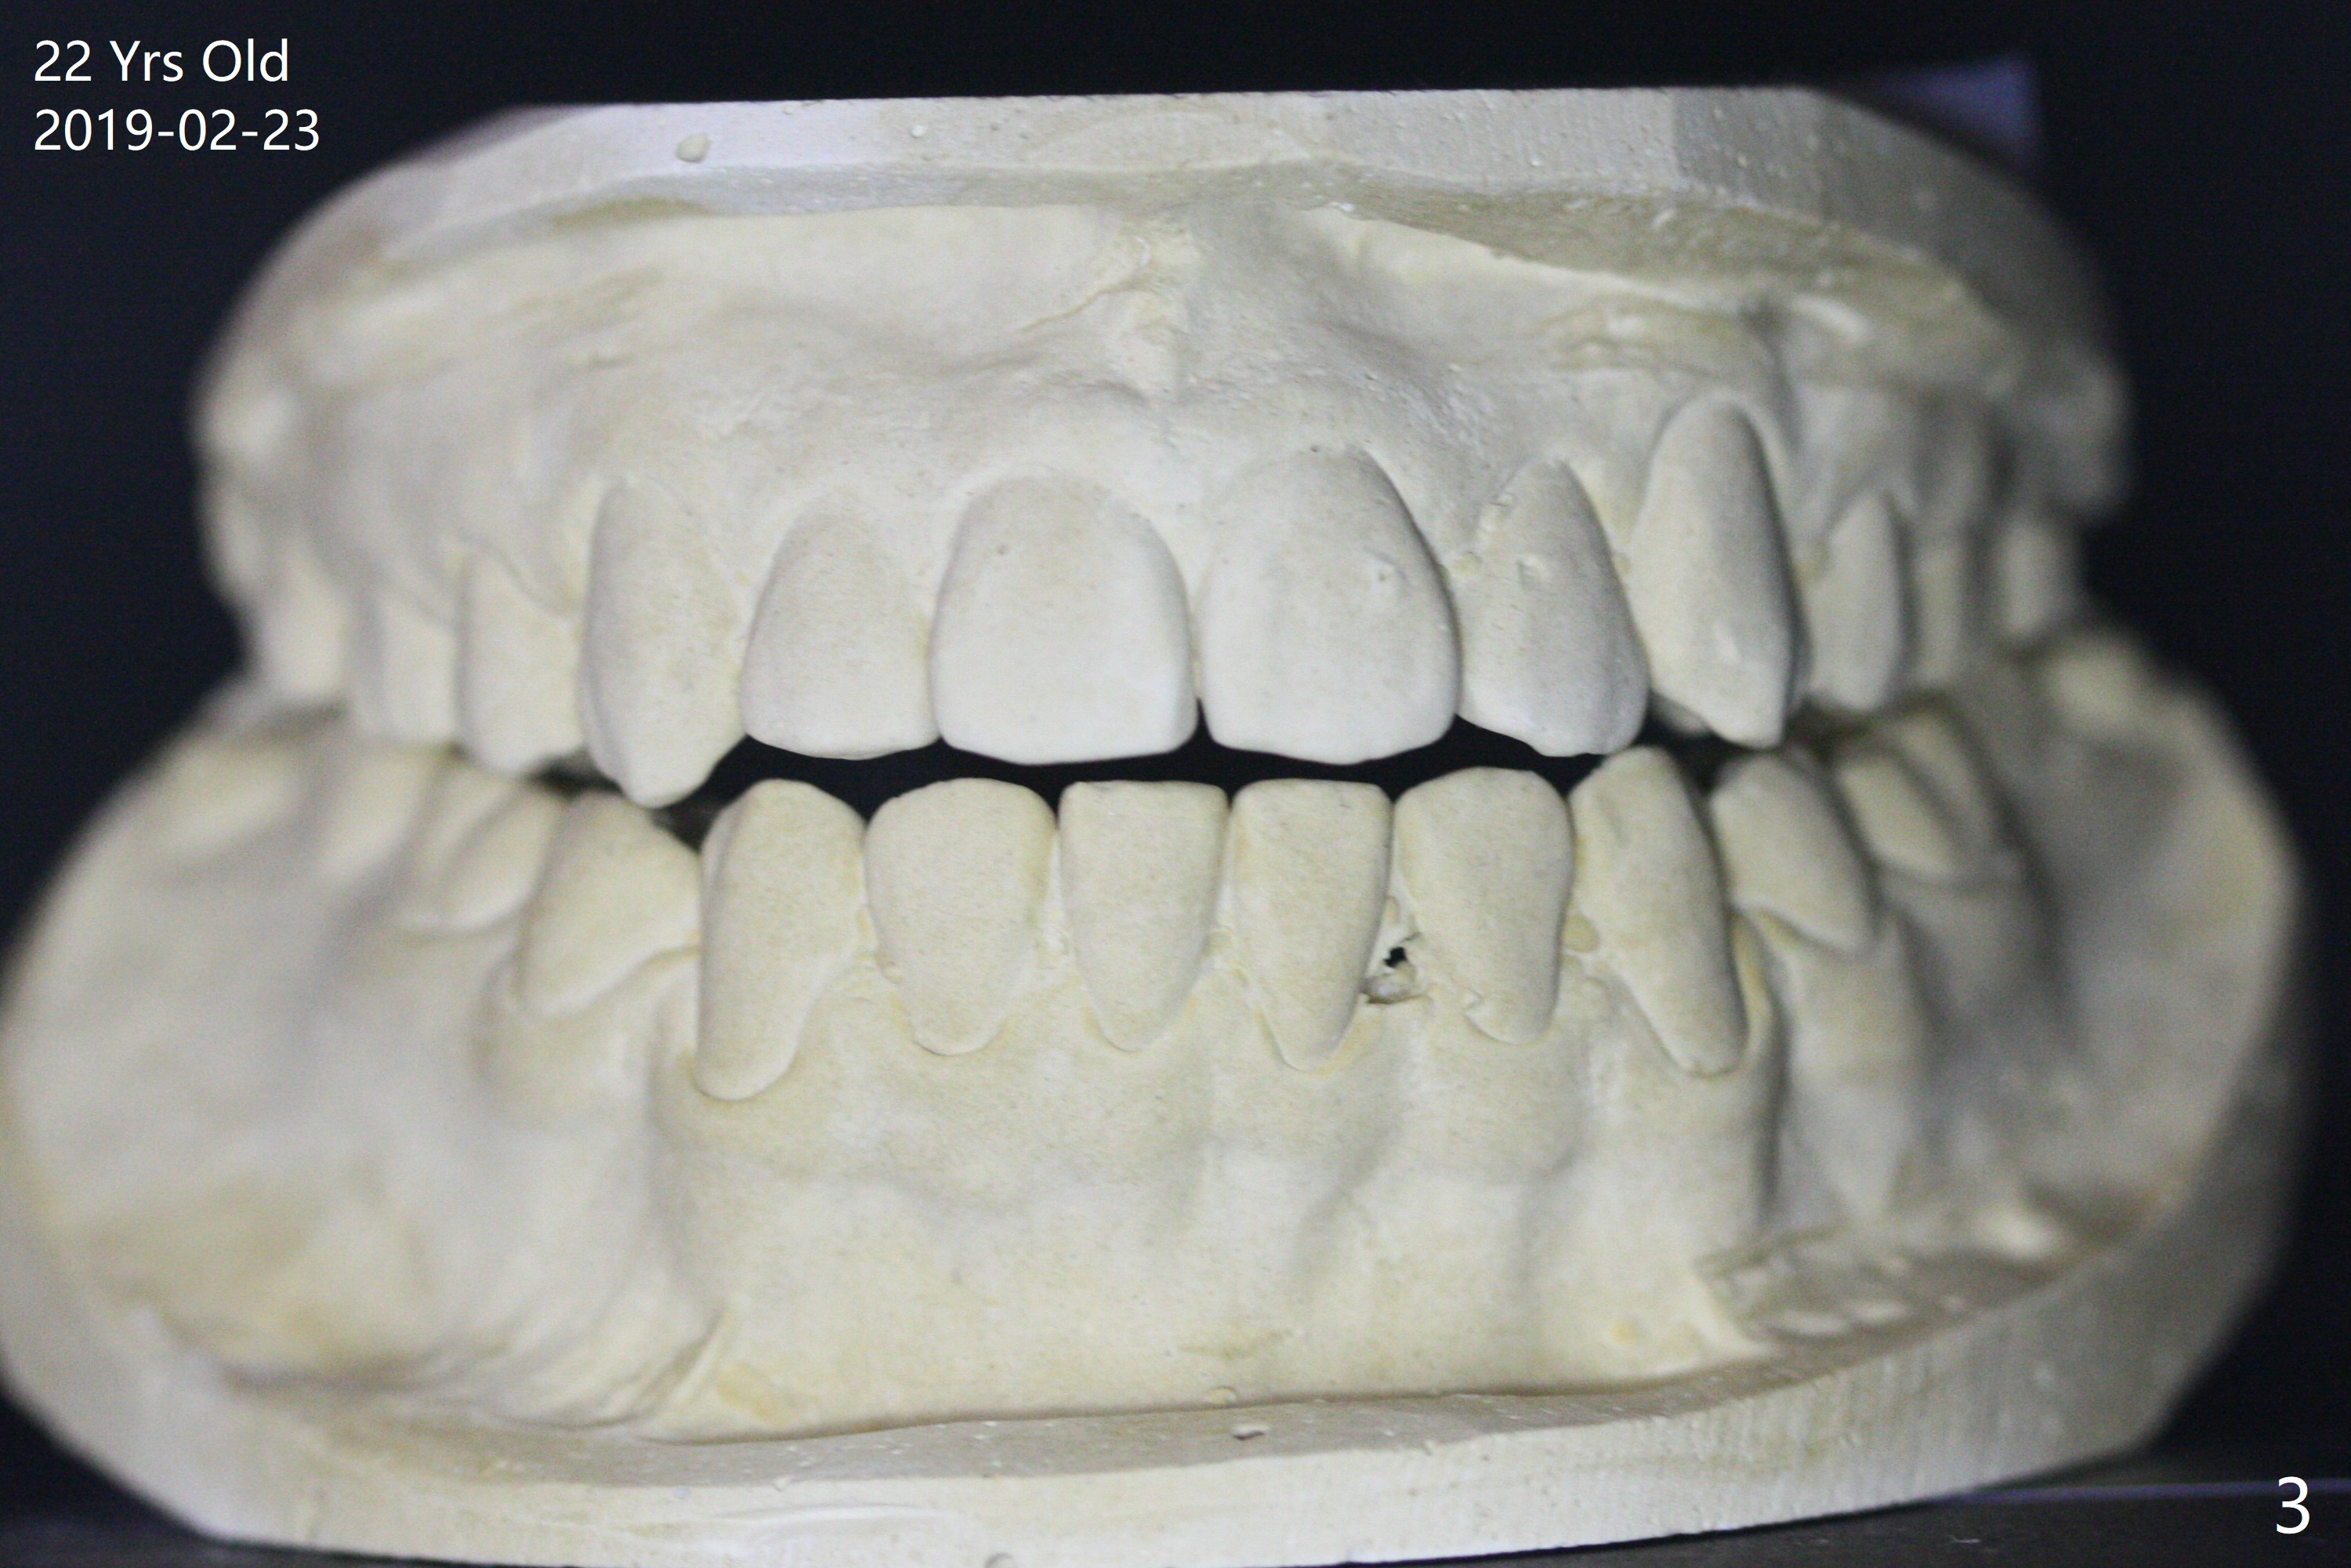

A 16-year-old man has severe crowding, but the open bite is ignored (Fig.1,4,7,10,13). The orthodontic treatment lasts 4 years 5 months, including failure to return for a period of time. The open bite seems to have been corrected (Fig.2, 5, 8, 11, 14). Suction down retainers are provided. In less than 2 years, the patient returns requesting remaking retainers. It appears that open bite relapses (Fig.3,6,9,12,15), as related to supraeruption of the lower 2nd molars (Fig.6,9 arrows). The latter is apparently associated with the erupting 3rd molars.